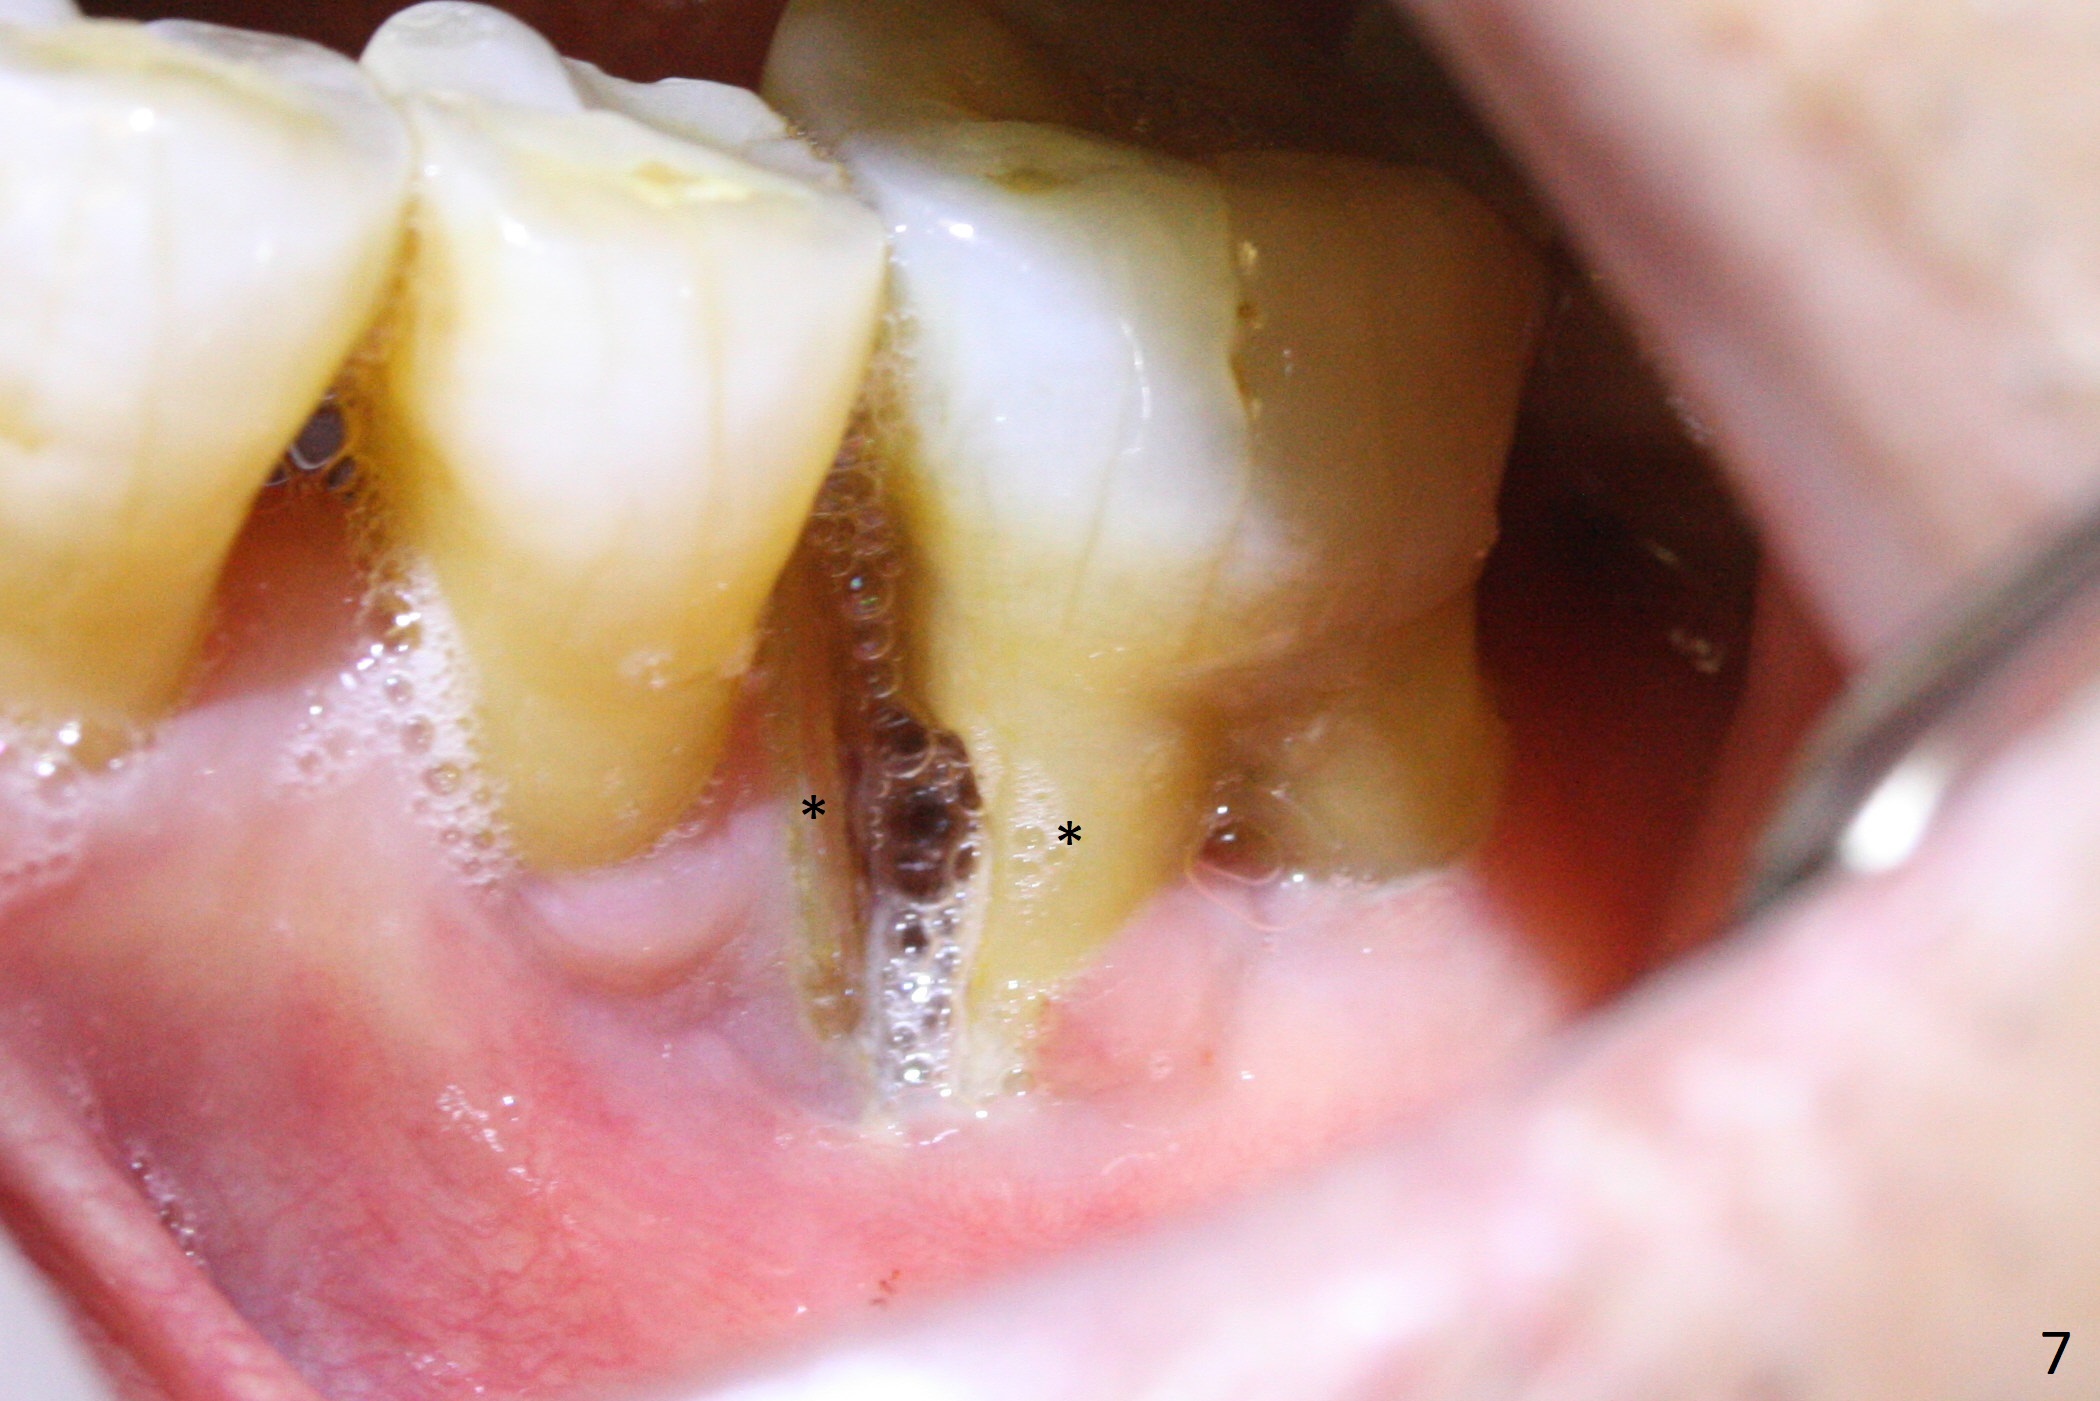

A 63-year-old man is a diabetic with history of good control. He masticates unilaterally with missing teeth #2,3 and 24 (Fig.1 (taken 5 years ago)). The latter has been restored with an implant. Last February the mesial root of the tooth #19 was found to have vertical fracture with bone loss until the base of the septum (Fig.2). The bone available for implantation is ~7-8 mm after root fracture (Fig.3,4). The initial osteotomy depth will be 7 mm (IS kit), followed by the calibrated parallel pin. The latter determines how many millimeters of an implant will be surrounded by the graft bone (Fig.4,5 (green: implant length; pink: cuff; blue: abutment length)). Since the buccal defect is severe with mesial root split (Fig.7 *), draw blood for PRF (2 large tubes). To save the remaining septum, place 2 of 1-piece implants on the either side of the septum (compare Fig.6,8). Take photos to compare buccal vs. lingual gingival recession. Tell the patient that the tooth #20 may be nonsalvageable. Since insurance preauthorization does not get approval for several times, the tooth #19 is extracted with socket preservation and periodontal dressing. The latter dislodges in 1 day. When the patient returns for follow up 4 days postop, the socket is exposed (Fig.9). An immediate implant should have been placed to keep the graft in place. PRF also helps. In fact preauthorization letter arrived 1 day earlier. It appears that guided surgery is indicated for limited bone height. The bone graft appears to gain ~ 5 mm bone in 4 months (Fig.10), which allows to place a 5x8.5 mm implant (Fig.11).